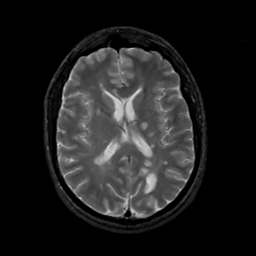

MR Study #12, May 12, 1991 -- Slice #29

[Home][Help][Clinical][Tour 1][Tour 2] Slice 29